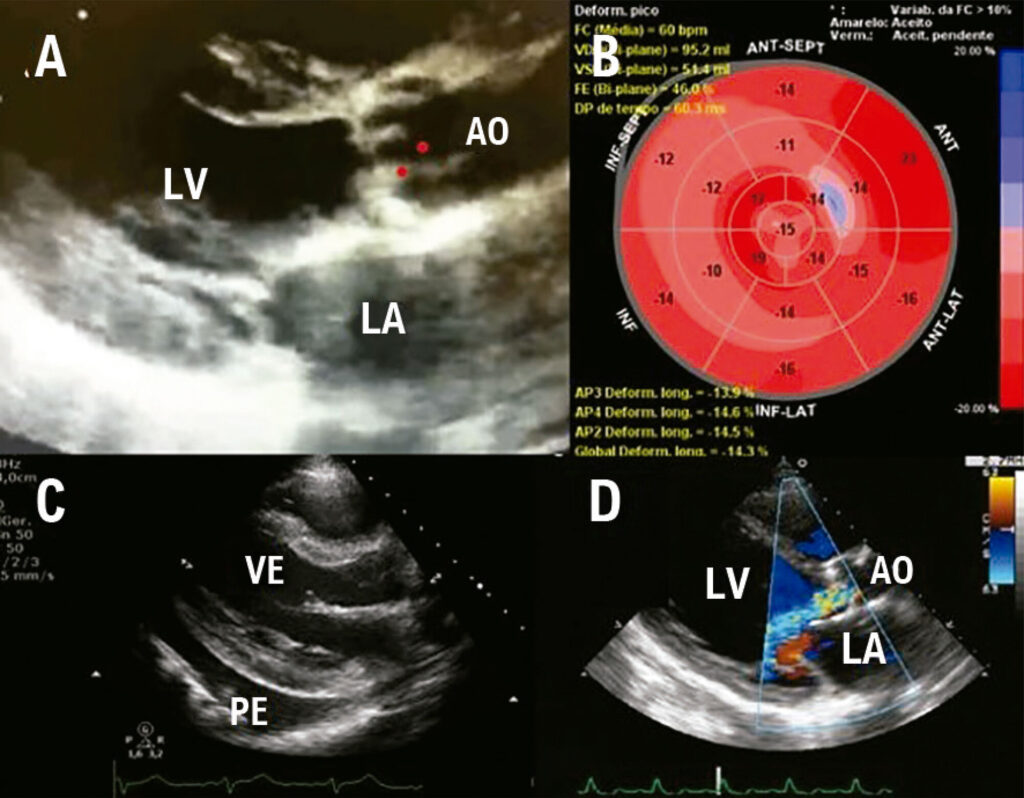

Radiotherapy-Induced Heart Disease: What Can We Evaluate?

Radiotherapy (RT) has been part of oncological treatment since 1899 and is currently used with more than 50% of all patients. Breast, lung, esophagus, and lymphoma tumors are commonly submitted to RT treatment, showing improvements in the total survival and freedom from diseases. By contrast, when including mediastinal structures, such as the heart and blood vessels, in 10% to 30% of the patients, adverse cardiovascular events were observed after 5 and 10 years, defined as Radiation-Induced Heart Disease (RIHD).,

The RIHD spectrum includes pericardial diseases, coronary artery disease, valvar heart disease, cardiomyopathy, as well as conduction abnormality and dysautonomia, leading to an increase in the cardiovascular morbidity and mortality of the survivors.